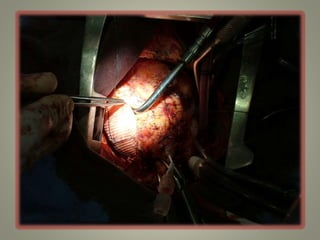

Técnica Cirúrgica